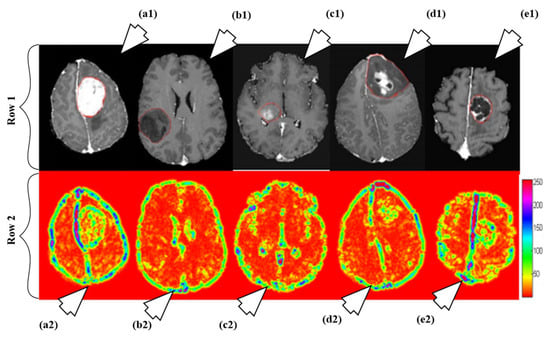

6.1.4. A Multi-Parametric Tissue Characterization System for Brain Neoplasm

- Ryu, Y.J.; Choi, S.H.; Park, S.J.; Yun, T.J.; Kim, J.H.; Sohn, C.H. Glioma: Application of whole-tumor texture analysis of diffusion-weighted imaging for the evaluation of tumor heterogeneity. PLoS ONE 2014, 9, e108335. [Google Scholar] [CrossRef] [PubMed]